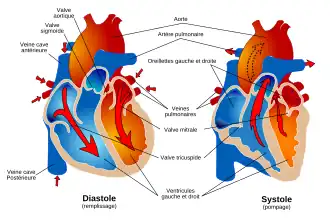

Cycle cardiaque

Diastole et

Systole auriculaire

Systole ventriculaire

La fréquence cardiaque au repos chez l'Homme est de 60 à 80 battements par minute, pour un débit de 4,5 à 5 litres de sang par minute. Au total, le cœur peut battre plus de 2 milliards de fois en une vie. Chacun de ses battements entraîne une séquence d'événements collectivement appelés la révolution cardiaque. Celle-ci consiste en trois étapes majeures : la systole auriculaire, la systole ventriculaire et la diastole :

- Au cours de la systole auriculaire, les oreillettes se contractent et éjectent du sang vers les ventricules (remplissage actif). Une fois le sang expulsé des oreillettes, les valves auriculo-ventriculaires entre les oreillettes et les ventricules se ferment. Le sang continue tout de même à affluer dans les oreillettes. Ceci évite un reflux du sang vers les oreillettes. La fermeture de ces valves produit le son familier du battement du cœur.

- La systole ventriculaire implique la contraction des ventricules, expulsant le sang vers le système circulatoire. En fait, dans un premier temps, très bref, les valvules sigmoïdes sont fermées. Dès que la pression à l’intérieur des ventricules dépasse la pression artérielle, les valvules sigmoïdes s'ouvrent. Une fois le sang expulsé, les deux valves sigmoïdes - la valve pulmonaire à droite et la valve aortique à gauche - se ferment. Ainsi le sang ne reflue pas vers les ventricules. La fermeture des valvules sigmoïdes produit un deuxième bruit cardiaque plus aigu que le premier. La pression sanguine augmente.

- Enfin, la diastole est la relaxation de toutes les parties du cœur, permettant le remplissage (passif) des ventricules (plus de 80 % du remplissage dans les conditions usuelles), par les oreillettes droite et gauche et depuis les veines cave et pulmonaire. Les oreillettes se remplissent doucement et le sang s'écoule dans les ventricules.

Le cœur au repos passe un tiers du temps en systole et deux tiers en diastole.